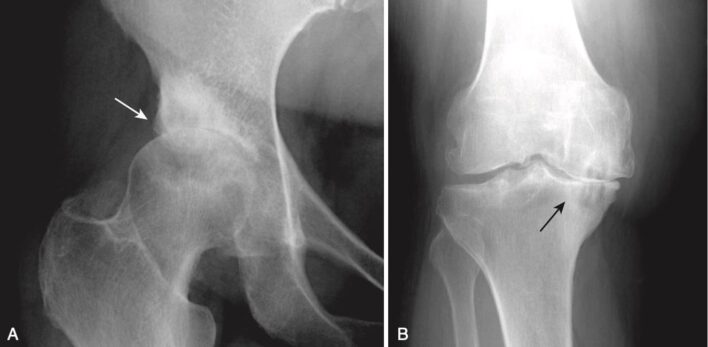

Hình 2. Hình ảnh nào là viêm khớp? A, Có hẹp khe của khớp háng, và cả chỏm xương đùi và ổ cối đều bất thường (mũi tên trắng). Đây là bệnh thoái hóa khớp háng. B, Có bất thường chỏm xương đùi (đặc xương), nhưng khe khớp còn nguyên vẹn, cũng như ổ cối (mũi tên đen). Đây là hoại tử vô mạch của chỏm xương đùi.

Hình 5. Thoái hóa khớp háng (A) và gối (B). Trong thoái hóa khớp, sự phá hủy của lớp sụn giữa các đầu xương dẫn đến hẹp khe khớp thường ở mặt chịu trọng lượng của khớp. A, Ở khớp háng, mặt trên và mặt ngoài chịu trọng lượng và do đó bị ảnh hưởng nhiều nhất (mũi tên trắng), trong khi ở gối (B), khoang trong chịu trọng lượng và bị ảnh hưởng nhiều hơn (mũi tên đen).